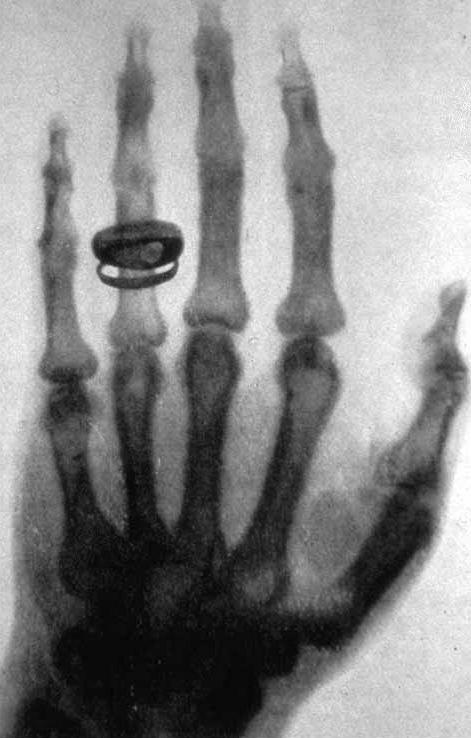

Mentre era intento a studiare il comportamento dei raggi catodici, si accorse che qualcosa di strano stava accadendo. Il foglio di carta su cui era stata scritta la lettera “A” con una soluzione di platinocianuro di bario brillava grazie alla luce emessa dai raggi invisibili provenienti dal tubo a vuoto con cui stava lavorando. Sorpreso e affascinato da quel fenomeno avvicinò la sua mano e lasciò che quel fascio di luce l’attraversasse. L’ombra delle ossa della sua mano appariva adesso sul foglio. Come fermare quel magico istante nel tempo? Röntgen ebbe una geniale intuizione: sostituire il foglio bianco con una lastra fotografica. Adesso era in grado di vedere com’erano gli oggetti al loro interno senza romperli e di conservare quelle immagini nel tempo. Non sapeva bene di cosa si trattasse e proprio per questo li definì raggi X, ma era sicuro si trattasse di qualcosa di straordinario e profondamente innovativo. Era la notte dell’8 novembre 1895.

Anna Bertha Ludwing e la prima radiografia della storia

Anna sostenne sempre il marito con grande impegno e con tutte le forze che aveva. Quando Wilhelm trascorse sette settimane isolato nel proprio laboratorio verso la fine del 1895, non solo si prese cura di lui, ma si prestò anche ad essere la prima cavia di quella che sarebbe stata una delle più grandi innovazioni scientifiche. Fu la protagonista della prima radiografia della storia esponendo per 15 minuti la sua mano ai raggi X. Cosa apparve nell’immagine che venne registrata? Le ossa della sua mano sinistra con tanto di anello nuziale sull’anulare. Sconvolta per aver visto le proprie ossa mentre era ancora in vita, Anna non mise mai più piede nel laboratorio di suo marito.